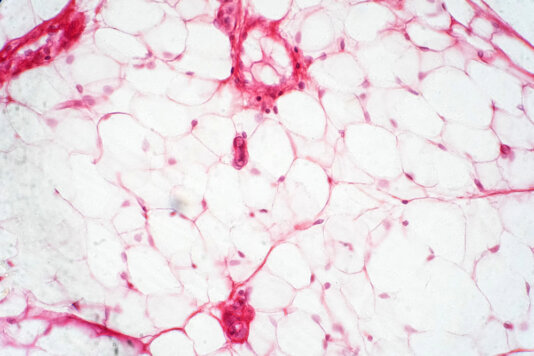

Darüber hinaus ist Fettleibigkeit eine stigmatisierte und "verpönte" Erkrankung, nach dem Motto: man habe sich nicht im Griff. Das stimmt jedoch nicht. Genetisch ist uns eine bestimmte Art der Verstoffwechslung von Nahrung von Natur aus mitgegeben. Diese können wir nicht ändern. Manche Menschen sind Meister in "Lipogenese", d.h. sie bilden bei jeder Mahlzeit so viele Fettreserven wie möglich, quasi "für den Notfall", für die nächste Hungersnot.

Noch heute wird unterschätzt, wie viele fettleibig sind, weil sie eine Eßstörung haben, sei es als eine psychiatrische Erkrankung, zum Beispiel Binge Eating, sei es als Folge von Medikamenten. Eine vermehrte Fettgewebe-Bildung kommt auch bei Menschen mit verschiedenen angeborenen oder später auftretenden Stoffwechselerkrankungen, wie z.B. Morbus Cushing, vor